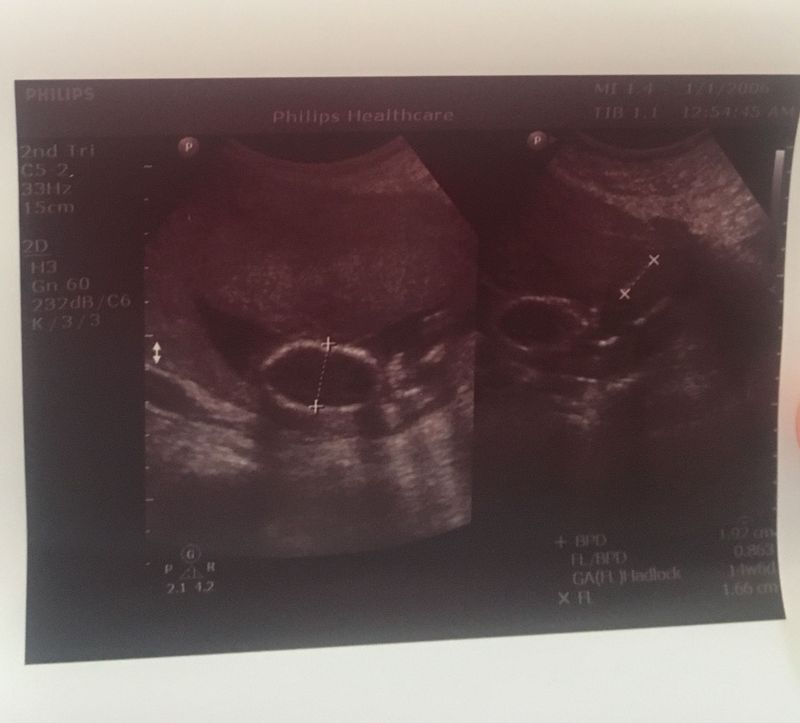

A missed abortion is a miscarriage in which your fetus didn't form or has died, but the placenta and embryonic tissues are still in your uterus. It's known more commonly as a missed miscarriage. It's also sometimes called a silent miscarriage. A missed abortion is not an elective abortion.